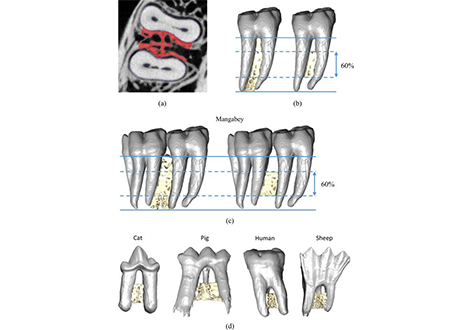

Alveolar bone, together with the underlying trabecular bone, fulfils an important role in providing structural support against masticatory forces. Diseases such as osteoporosis or periodontitis cause alveolar bone resorption which weakens this structural support and is a major cause of tooth loss. However, the functional relationship between alveolar bone remodelling within the molar region and masticatory forces is not well understood. This study investigated this relationship by comparing mammalian species with different diets and functional loading (Felis catus, Cercocebus atys, Homo sapiens, Sus scrofa, Oryctolagus cuniculus, Ovis aries). We performed histomorphometric analyses of trabecular bone morphology (bone volume fraction, trabecular thickness and trabecular spacing) and quantified the variation of bone and tooth root volumes along the tooth row. A principal component analysis and non-parametric MANOVA showed statistically significant differences in trabecular bone morphology between species with contrasting functional loading, but these differences were not seen in sub-adult specimens. Our results support a strong, but complex link between masticatory function and trabecular bone morphology. Further understanding of a potential functional relationship could aid the diagnosis and treatment of mandibular diseases causing alveolar bone resorption, and guide the design and evaluation of dental implants.

The image stacks were segmented using a ray casting algorithm which differentiated bone and teeth from non-bone/teeth material, using the grey-level gradient of the image.